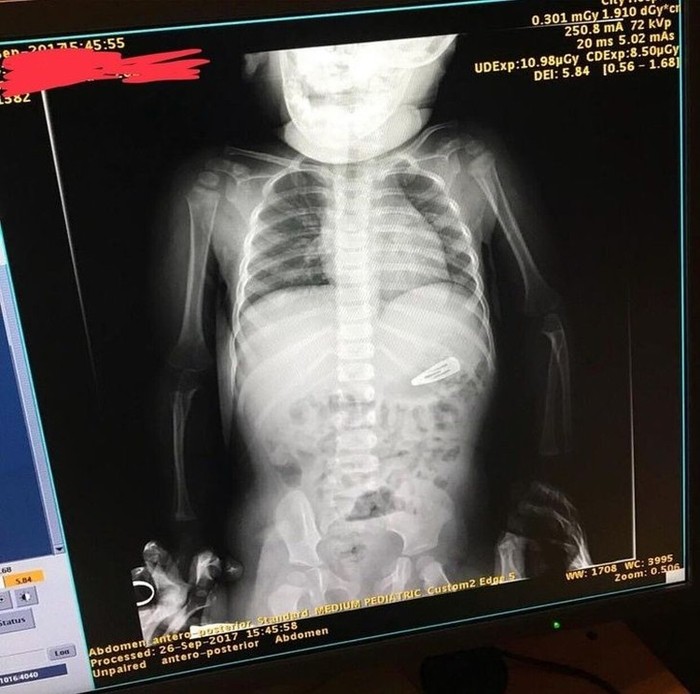

Ada-ada saja,anak gadis ini menelan jepitan rambut. (Foto: Brightside)